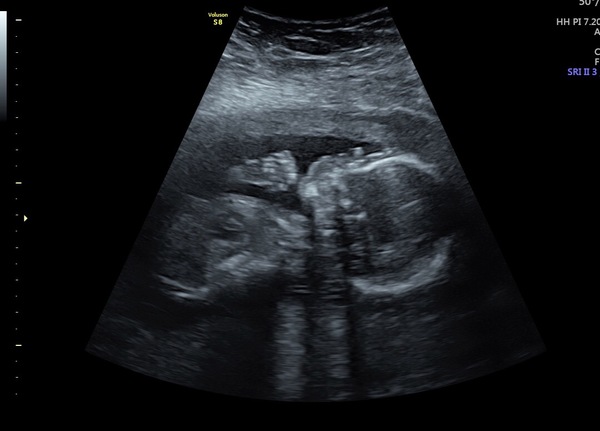

Hi ladies I hope you’re all okay! Such a scary time at the min, anxiety has been getting the best of me so decided to get a private scan at 16 weeks to check in and let husband see baby too. All my scans with lily brought bad news, so I get so scared but everything was fine and we found out baby no 2 is a boy! 18 weeks on Saturday, still terrified but just trying to enjoy it!